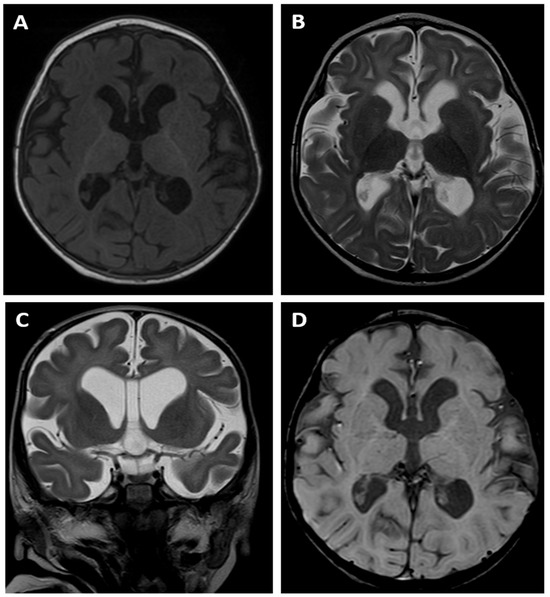

The brain MRI examination performed at the age of 6 months (Figure 1A,B) revealed a significantly enlarged cisterna magna and moderate dilatation of sulci in the frontal lobes, as well as moderate dilatation of the lateral and third ventricles as a feature of cortico-subcortical atrophy with an adjacent enlargement of the subarachnoid space in the fronto-temporal areas. There was also delayed myelination of the white matter, indicating a typical pattern for the age of 4 months (a high signal intensity of the splenium of the corpus callosum on the T1-weighted image). A follow-up MRI examination was performed at the age of 14 months (Figure 1C,D) and showed progression of the myelination process. However, there were still features of cortico-subcortical atrophy. Moreover, the cortex/white matter differentiation was blurred, especially on the T2-weighted image, instead of being clearly visible at this age, which could indicate a demyelination disorder.

Proband 1 and a 24-year-old female described by Moskowitz et al. have the same variant in the ZMYND11 gene. Both patients had global developmental delay, especially affected speech, hypotonia and delayed myelination in the MRI. However, unlike the case of the patient described by Moskowitz et al. [11], in the patient described in this paper, there was no evidence for us to diagnose epilepsy, although our patient had been receiving an antiepileptic drug for several years. The clinical characteristics of the presented patients and the literature references are shown in Table 1.

Moving onto neurological disorders in cases with ZMYND11 pathological variants, their range is immensely wide and includes generalised developmental delay, seizures, autism and behavioural abnormalities [6,7,11]. Among them, the presented patient 2 suffers from generalised developmental delay and seizures, which were diagnosed at 2 months of age. We believe that the ZMYND11 mutation also seems to have a significant impact on dysmyelination changes in the presented probands, which is confirmed by scientific reports. Cortico-subcortical atrophy of the cerebral cortex [1], cerebral atrophy, delayed myelination and compression of myelin [5,7,11] are MRI findings that have been reported in the papers published hitherto. These vastly coincide with the changes exhibited by our probands.

Figure 1. Brain MR examinations of patient 1: axial T1-weighted images (A,C) and axial T2-weighted images (B,D) performed at the age of 6 months (upper row) and at the age of 14 months (bottom row). The images show a feature of cortico-subcortical atrophy with an adjacent enlargement of the subarachnoid space in the fronto-temporal areas ((A,B)—red arrows). There is also delayed myelination of the white matter, indicating a typical pattern for the age of 4 months ((A)—white arrow pointing to a high signal intensity of the splenium of the corpus callosum on the T1-weigthed image). The follow-up MRI examination (C,D) revealed progression of the myelination process; the cortex/white matter differentiation is blurred, especially on the T2-weighted image ((D)—red arrows), instead of being clearly visible at this age, which can indicate a demyelination disorder.